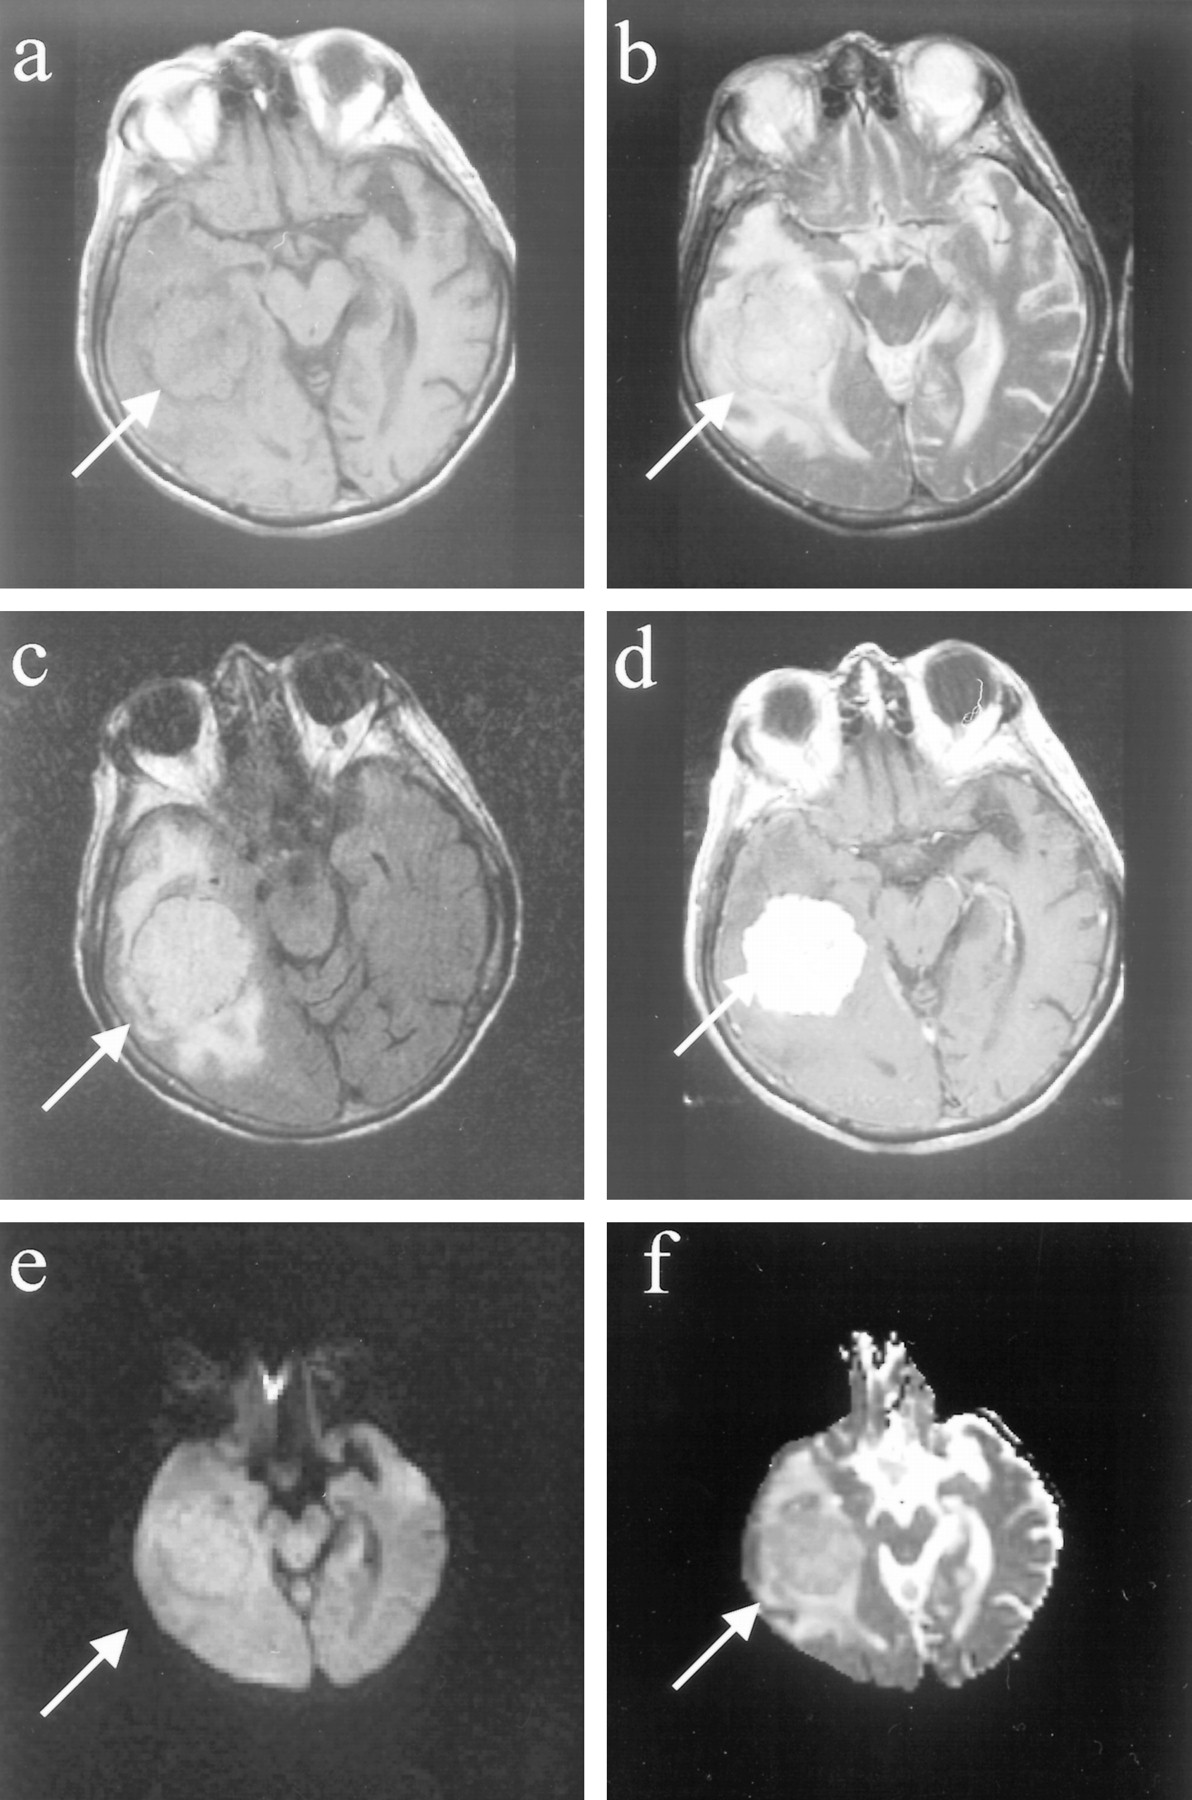

Thirteen (76%) of 17 meningiomas were benign as revealed by histopathologic examination (WHO grade I). On average, these meningiomas had an elevation in the diffusion constant (average, 1.03 ± 0.29 × 10−5cm2/s; range, 0.62−1.80 × 10−5cm2/s) (Fig 2, patient 9). These meningiomas were usually isointense on the short-TR images and predominantly hyperintense on the long-TR images. One of these benign meningiomas, which appeared densely calcified, had a diffusion constant below that of normal brain, overlapping the range of values observed in the malignant and atypical group. The other 12 meningiomas had diffusion constant values higher than that of normal brain, and none of these were densely calcified.

Images of a patient (patient 9 in the Table) with a benign meningioma (WHO grade I).

A, Axial T1-weighted image of right temporal meningioma with “pseudocapsule” sign.

B, Axial fast spin-echo T2-weighted image shows that the mass is slightly hyperintense to cortex.

C, Fast fluid-attenuated inversion recovery image shows mass to be hyperintense to cortex.

D, Contrast-enhanced T1-weighted image shows intense, homogeneous enhancement.

E, Mass is predominantly isointense/slightly hyperintense on the diffusion-weighted image.

F, On the ADC map, the mass appears isointense/hyperintense to cortex, with a diffusion constant value (0.93 × 10−5 cm2/s) that is slightly elevated compared with normal brain parenchyma.